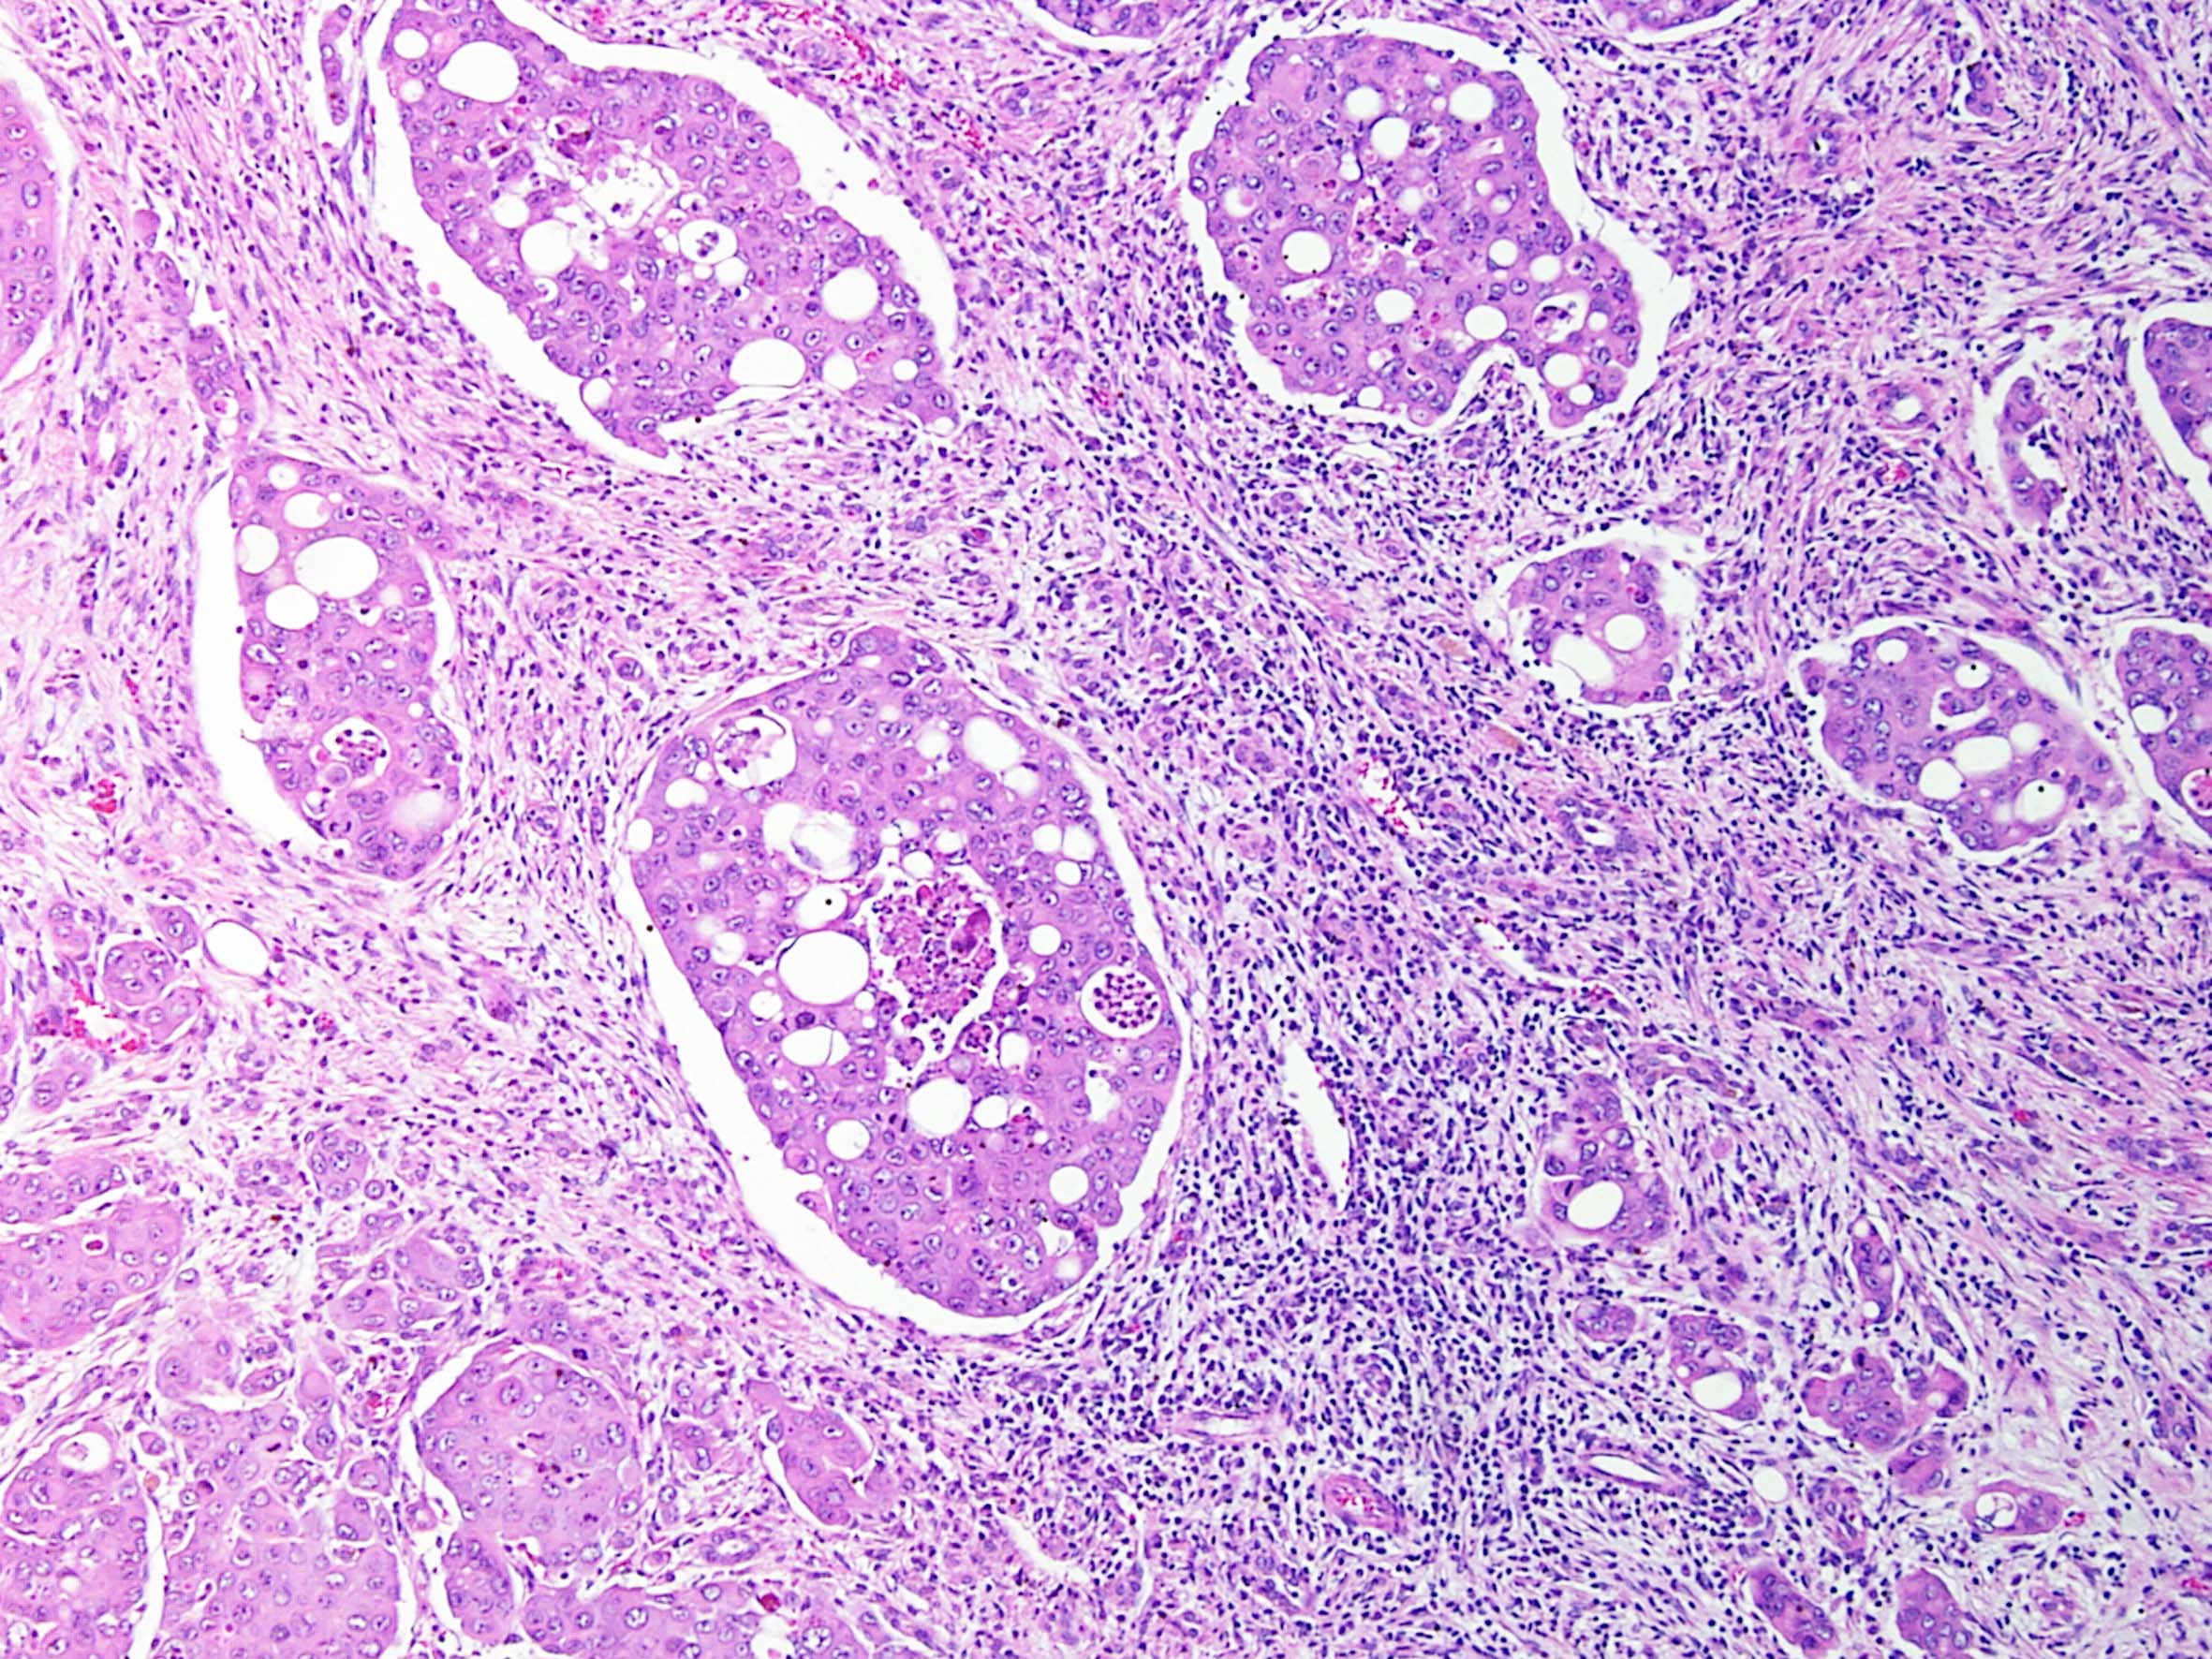

Consensus grade: Renal Medullary carcinoma

Case description (by case creator):

Renal medullary carcinoma